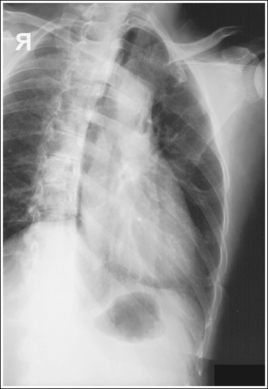

If breathing technique is not used, the details and cortical outlines of the posterior ribs, left scapula and lung markings are sharply defined, and the increased recorded detail obscures the details of the sternum (see Image 3).

IMAGE 3

• Evaluating accuracy of obliquity. When evaluating a PA oblique sternal projection, note that patient obliquity was sufficient when the sternum is located within the heart shadow and the manubrium and right SC joint are shown without vertebral superimposition. If the patient was not adequately rotated, the right SC joint and manubrium are positioned beneath the vertebral column (see Image 4). If patient obliquity was excessive, the sternum is rotated to the left of the heart shadow and the sternum demonstrates excessive transverse foreshortening (see Image 3).

The lung markings, posterior ribs, and left scapula are demonstrated without magnification or blurring, making it difficult to distinguish the sternum through these overlying structures. The SID was not shortened, and the patient's breathing was halted for this image. Also, patient obliquity was excessive, as indicated by the position of the sternum to the left of the heart shadow and by the amount of sternum rotation.

Shorten the SID to 30 inches (76 cm) if it is your facility's protocol, take the exposure while the patient is breathing shallowly, and decrease the degree of patient obliquity.